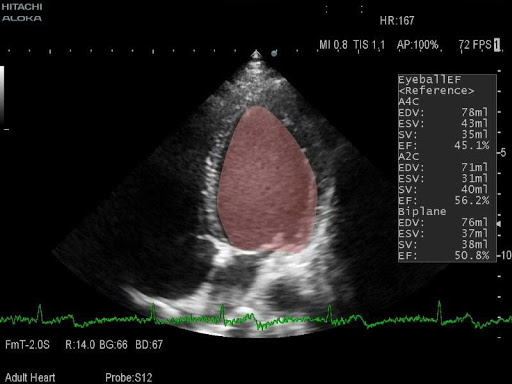

- Широкий кардиопакет

- Встроенные расчёты и измерения для всех типов исследований, включая кардио и TCD